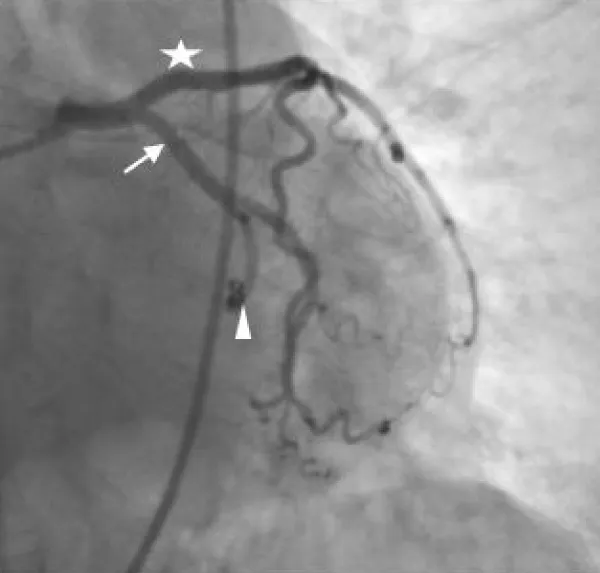

A diagnostic invasive angiography for the coronary arteries was done and showed a bizarre anatomy of the left circumflex coronary artery as it not only supplies the heart but also it continues its way to supply the left side of chest wall. Otherwise, the coronary arteries are patent with no stenosis noticed, Figure 1.

Figure 1: Percutaneous coronary angiography shows the anatomy of the coronary arteries. On A & B, the star refers to the left anterior descending artery, the arrow refers to the left circumflex coronary artery, and the arrow head refers to the abnormal branch of the LCX that continues to the intercostal arteries and the intercostal artery. C & D shows the course of the abnormal connection and the course of the intercostal artery. E shows the right coronary artery. Note that all coronary arteries have a patent lumen without stenosis./p>